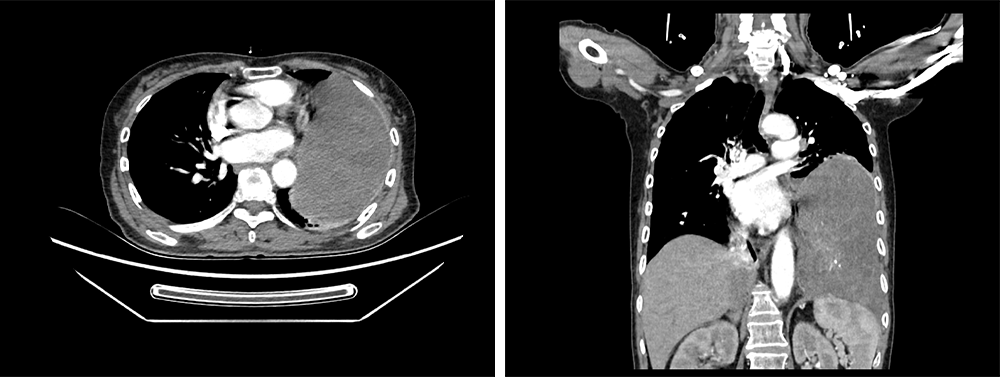

患者为一名67岁女性,因“乏力1个月余,发现左侧胸腔肿物10天”入院,入院时患者一般状态差,营养不良,体重仅有45kg,胸部CT增强检查显示:左侧胸腔肿物,边界强化,左肺受压不张,肿物边界不清,较大层面长径约15cm。同时常规检查发现血糖:1.79mmol/L,心电图:快速型房颤。

图1、图2 术前增强CT图像